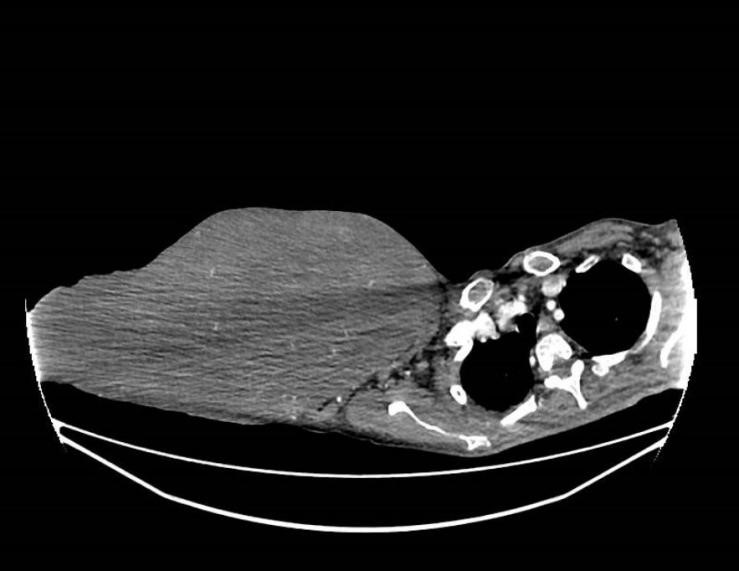

胸部增强CT影像。

入院后完善彩超、CT等检查,乳腺超声提示右侧乳腺巨大实行肿物,不排除恶性可能。胸部CT提示右侧乳腺见一巨大软组织密度肿块影,大小约318x120x425毫米(上下径)。PET-CT检测提示未见肿瘤转移。予行肿物切取活检,病理提示考虑叶状肿瘤。